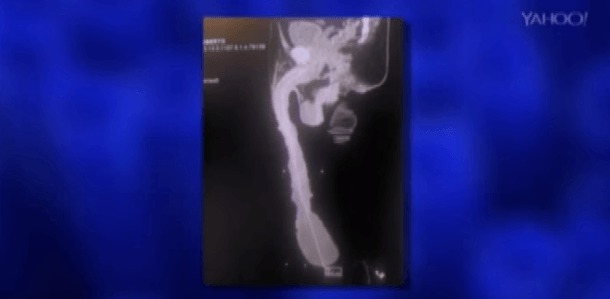

Contrairement à ce que l’on pourrait croire, cet attribut hors norme ne lui donne pas plus de succès auprès des femmes. Même pire ! Son sexe qui irait jusqu’au genou les ferait fuir ! En fait, une radiographie de son pénis a révélé que son membre ne mesurait « que » 15 cm et que son apparence serait dûe à un excès de peau de trente centimètres ! Il a finalement prévu une opération chirurgicale lui permettra de retrouver une vie normale.